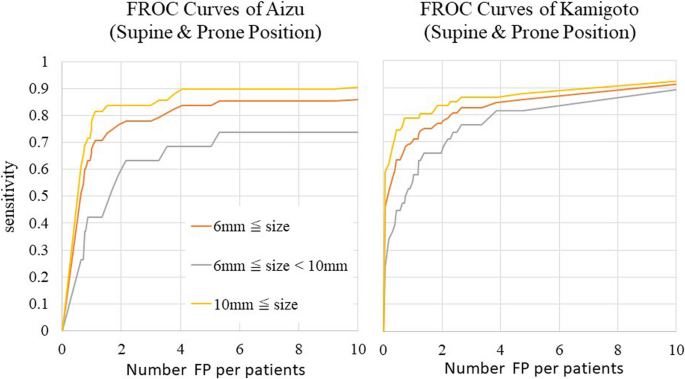

Fig. 8 also shows FROC curves per patient in the external validation dataset. Regarding the detection performance for each patient, if a correct lesion could be detected in either the supine or the prone position, then this was considered detection success, and the sensitivity was calculated. The number of FP lesions was the average value of the lesions detected in the supine and prone positions. The sensitivities for lesions ≥6 mm and lesions ≥10 mm when four FP lesions were allowed were 0.835 and 0.894 with the Aizu dataset and 0.848 and 0.866 with the Kamigoto dataset, respectively. Using this method, the sensitivity improved compared to that observed when evaluating each CT series in one position. Additionally, even for 6 to 10 mm lesions, the sensitivities when four FP lesions were allowed were improved, with values of 0.684 and 0.816, respectively. During the evaluation per patient, a plateau of the sensitivity was confirmed even after increasing the allowed number of FP lesions.

Sensitivities of the external validation dataset per patient by FROC analysis. Regarding the sensitivities for each patient, if a correct lesion could be detected in either the supine or the prone position, then this was considered detection success, and the sensitivities was calculated.

A comparison of the sensitivity using the CT series with one position and the sensitivity for each patient in two positions is shown in Table 3. There was no difference in the sensitivities obtained in the supine and prone positions using both the Aizu and Kamigoto datasets when the number of FP lesions was allowed to be as high as 4 or 8. When comparing the sensitivity of the two position combinations with single position (supine or prone), we found that there was an improvement of 16.0 - 32.1% for FP=4 and 14.4 - 38.0% for FP=8, which were statistically significant at p < 0.05 in McNemar statistical test.